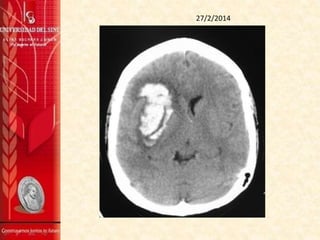

7/3/2014

TAC DE CRÁNEO SIN CONTRASTE 7/3/2014

Se observa una imágen hiperdensa que compromete la

región ganglio-basal derecha, de contornos difuminados, de

aproximadamente 40 mm por 19 mm, en el plano axial con

aspecto de hematoma intraparenquimatoso, sus contornos

hacen pensar en una evolución hacia la cronicidad.

Hay discreto efecto de masa dado por el edema alrededor de

la lesión que está desviando la línea media unos 7 mm a la

izquierda.

No se aprecian masas extra axiales.

La fosa posterior es normal.

IMPRESIÓN:

1. Hematoma intraparenquimatoso en la la región ganglio-

basal derecha.

7 MARZO 2014